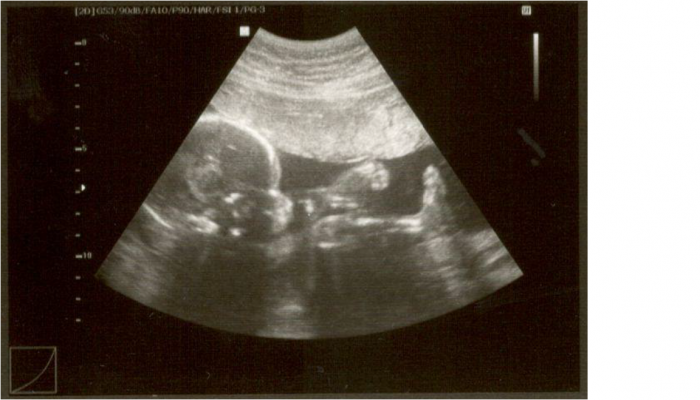

[1005217] Holky, už se to rovná, moc děkuji a omlouvám se za odpolední výlev emocí... Pokusím se vložit obrázek našeho nejspíš Honzíka...

[1005244] jani pěkná fotečka. I jméno.taky máme doma Honzíka

[1005244]Jani moc krásná fotka a Honzík je pěkný jméno.. můj nejmladší bráška je taky Honzík.Za výlevy se omlouvat nemusíš, prostě s tebou zacloumaly hormony..to tady myslím chápeme všechny